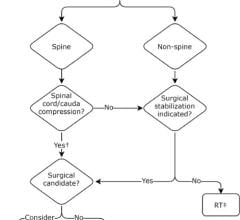

TomoDirect was developed as a complement to helical TomoTherapy, with both modes utilizing the same binary multi-leaf collimator and CT-style gantry technology, and sharing a simple, consistent treatment planning and delivery process. The choice of which modality to use for a given case will depend on the nature of the tumor volume and surrounding organs at risk. TomoDirect allows clinicians to choose several discrete angles as well as the optimal modulation level required for delivery. It is expected to provide significant time savings in both the planning and delivery phases for several clinical scenarios, including whole breast irradiation and palliative treatments. In addition to the added capabilities offered by TomoDirect, the Hi·Art system’s treatment modes are being expanded to include 3D conformal delivery, thereby providing a comprehensive range of options for all clinical cases.